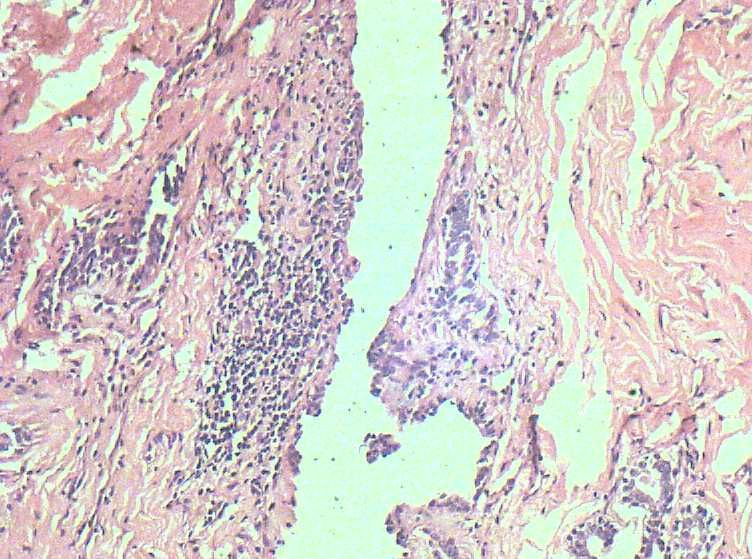

女41岁,左腺包块。肉眼:不整形囊壁样组织,大小2*1.6*0.3CM,壁厚0.1—0.3,未触及结节,未见出血及坏死。

• 乳腺积乳性包块?图2

图2

似乎有导管扩张、慢性炎细胞浸润、大汗腺化生、普通型导管增生等病变,没有看到囊壁内衬上皮或囊壁结构。

这例报了 慢性囊性乳腺病。不知可否?

乳腺腺病伴普通型导管增生

报乳腺增生性腺病伴导管上皮不典型增生。

。图12-16可以看到导管上皮异形增生(导管上皮极向紊乱)